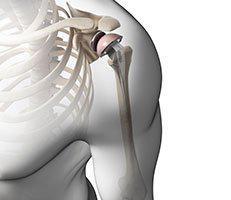

OrthoCincy Wellington Orthopaedics and Sports Medicine has provided quality orthopaedic care to patients in the greater Cincinnati area for more than 50 years. The practice has four locations in Cincinnati, a location in West Chester, Ohio, and an office in Highland Heights, Kentucky. With a large team of highly experienced physicians providing patients with specialized expertise in orthopaedic surgery, physical medicine and rehabilitation, regenerative medicine, podiatry, and sports medicine, the practice has the perfect doctor for every patient.

Each physician at OrthoCincy Wellington Orthopaedics and Sports Medicine works closely with physical therapists, hand therapists, and other clinical specialists in areas such as bracing and orthotics to create an individualized treatment plan. Thanks to their expertise in musculoskeletal treatment, research, and education, OrthoCincy Wellington Orthopaedics and Sports Medicine remains one of the largest and most respected centers in Cincinnati and the surrounding Tri-State Area.

The practice even works with Professional, collegiate, high school and developmental youth programs. From trained athletes to patients struggling with musculoskeletal conditions the specialists at OrthoCincy Wellington Orthopaedics and Sports Medicine have the experience, knowledge, and advanced treatment options to get patients back on their feet in no time. Call or book an appointment online today to learn more about the services they offer.